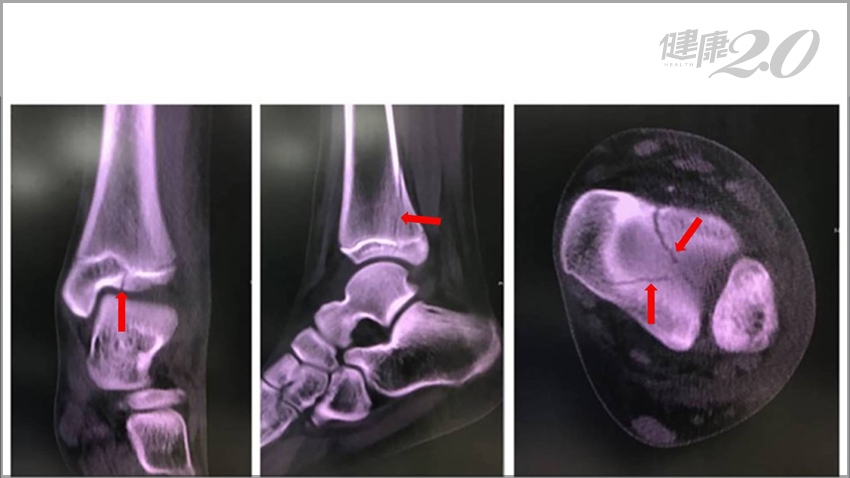

像張小妹妹這樣的骨折其實是很容易被忽略,在一般的X光上並不明顯,但在腳踝的電腦斷層上卻可以清楚看到複雜的骨折情形,這種情況稱之為踝關節遠端脛骨三平面型骨折 (Triplane fracture) 。

▲踝關節遠端脛骨三平面型骨折在X光上是無法看清楚。

▲在腳踝的電腦斷層上,可以清楚看到複雜的骨折情形。